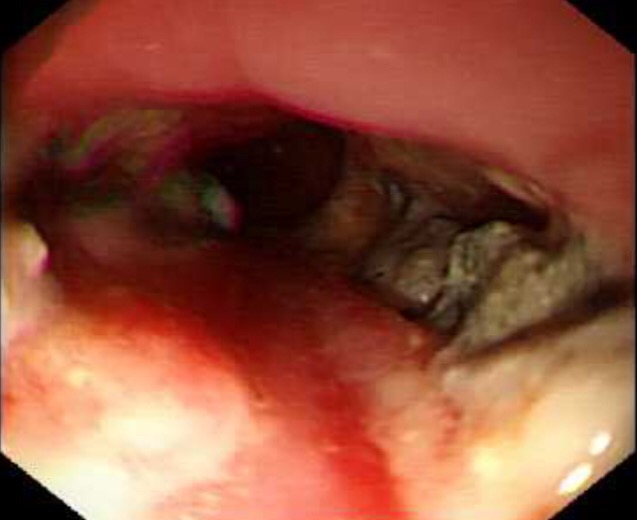

![]()

بطارية